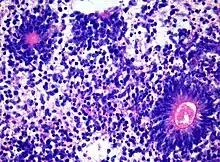

Histology of Medulloepithelioma

Medulloepithelioma, on the other hand, are tumors involving the constant cell division on the epithelium tissue where bundle of neuron endings are located.[1] Such tissue will differentiate into a similar form as the embryonic neural tube, also known as the starting structure of the central nervous system.[1][2][3] Medulloepitheliomas also present a pattern known as rosettes, characterized by the arrangement of a bundle of cells into circular shapes and around a center or a neuropil.[1] Ependymoblastoma also present rosettes as well as a higher density of cells.[1][3] It involves the process of differentiation into ependymal cells.[2][3]

Rosettes in Ependymoblastoma histology

Further classification types have come up but not yet approved by the World Health Organization.[1] The term "embryonal tumor with abundant neuropil and true rosettes", or ETANTR, has been proposed as a sixth subtype of PNET.[1] However, the still unofficial term "embryonal tumor with multilayered rosettes" (ETMR) has been more frequently used and encompasses ETANTRs, medulloepitheliomas, ependymoblastomas, and variants of PNETs with presence of rosettes and with no well defined classification.[3]